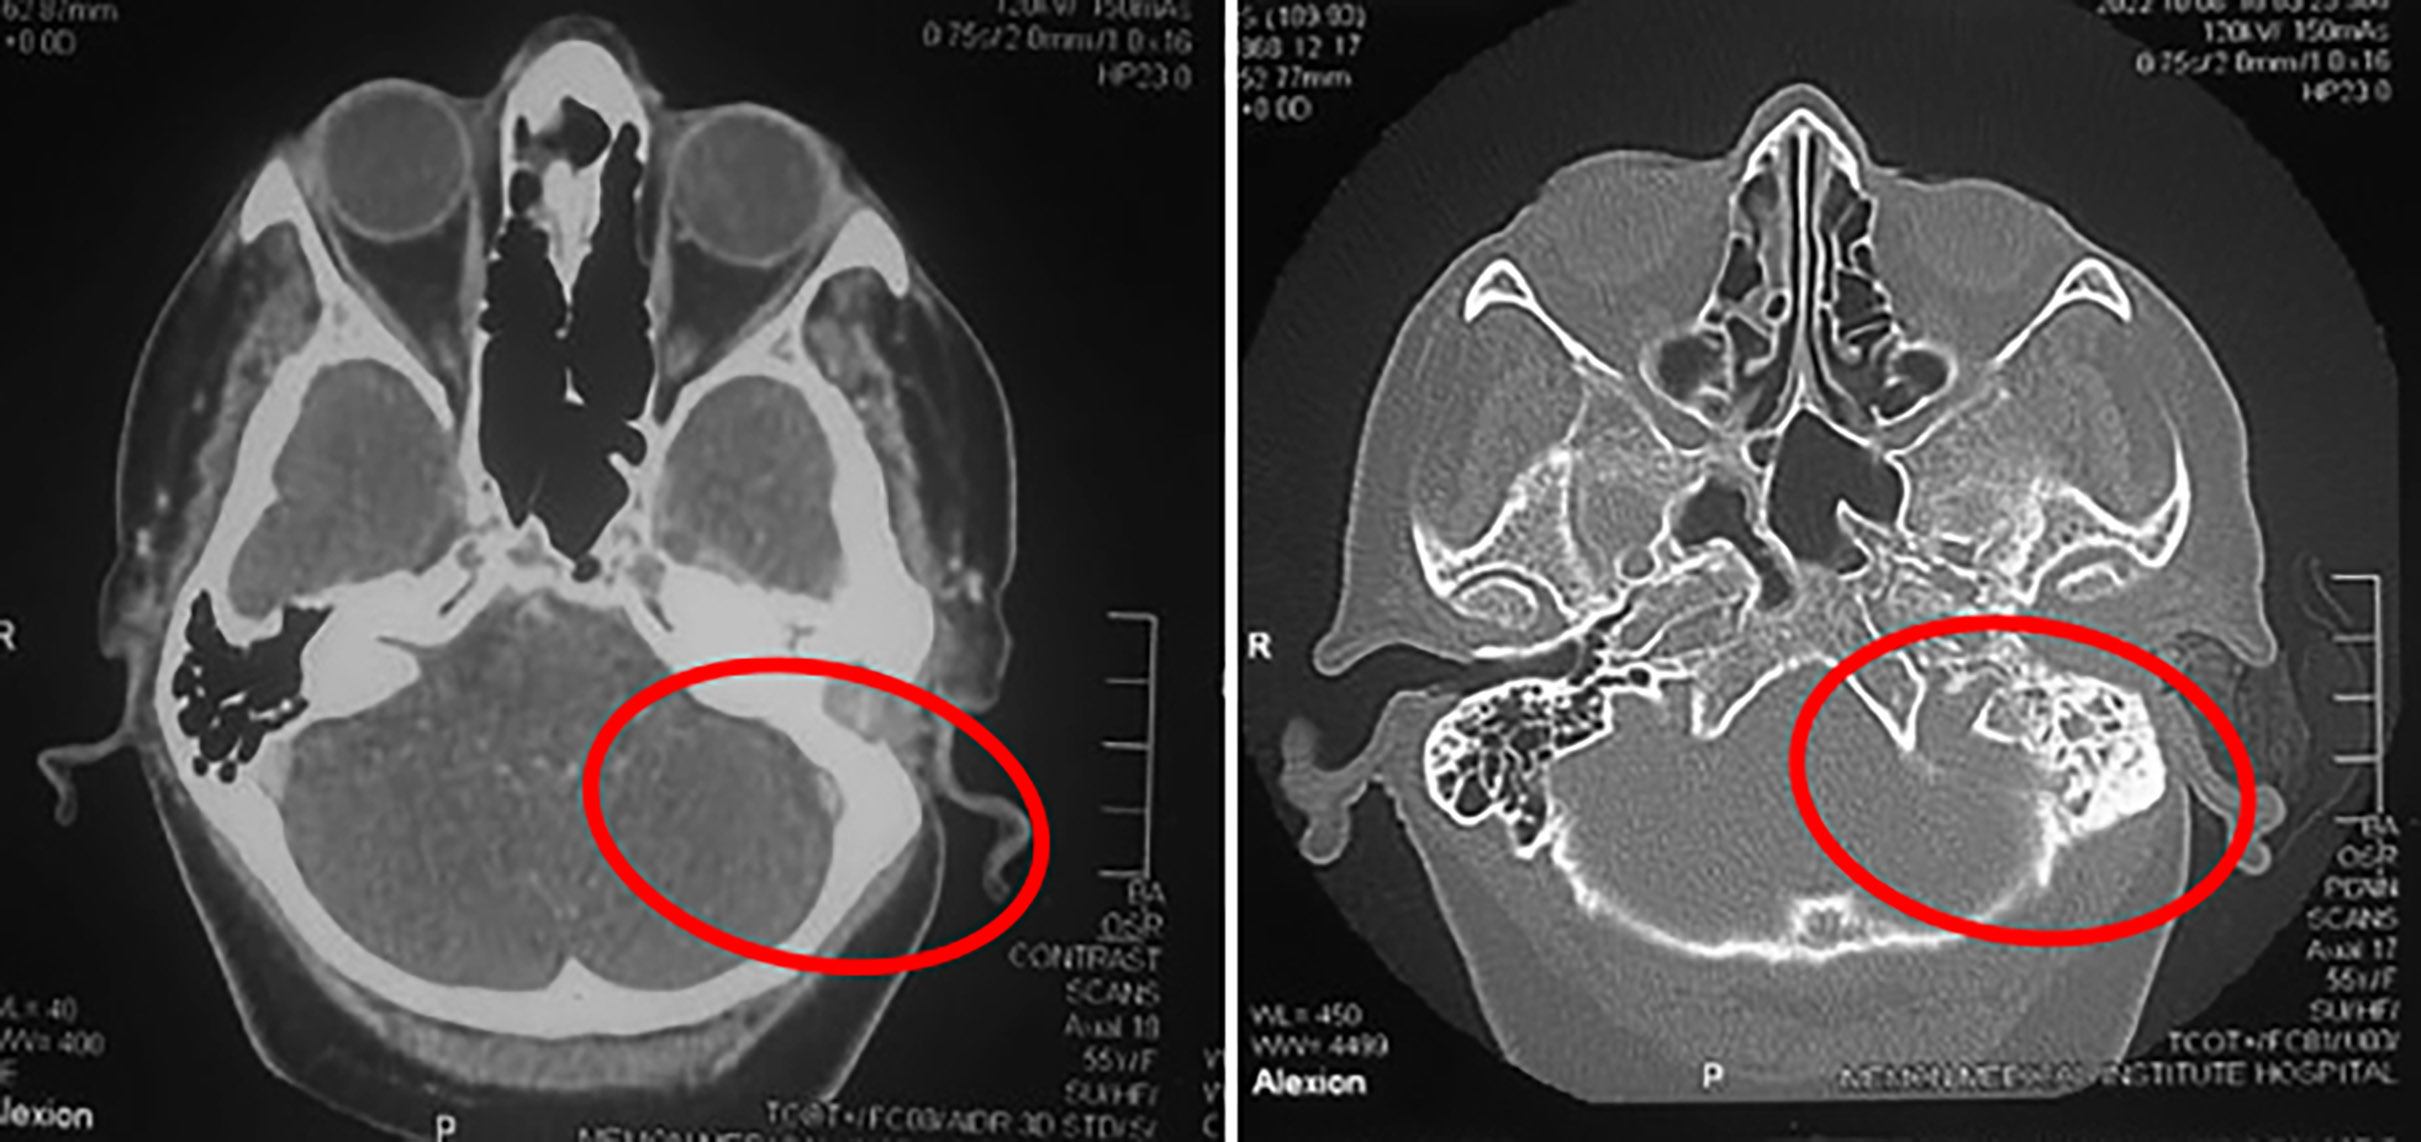

A CT scan of temporal bone with contrast reported a soft tissue mass in the left ear measuring 2.7 × 2.1 × 2.6 cm (TR × AP × CC) in dimensions (Figure 1) involving the left external acoustic meatus and mastoid air cells, with erosion of adjacent bone and attenuation of ossicles. A biopsy was taken under general anaesthesia due to the potential risk of bleeding. Histopathological examination led to the diagnosis of paraganglioma. According to the Modified Fisch classification, it was a Class-B2 tumour, involving the middle ear with extension to the hypotympanum and the mastoid.

Figure 1: CT scan of temporal bone with contrast (axial view). Right: Red outlined circle shows soft tissue mass occupying left external auditory canal and middle ear cavity with erosion of ossicles; left: Mastoid air cells are sclerotic.